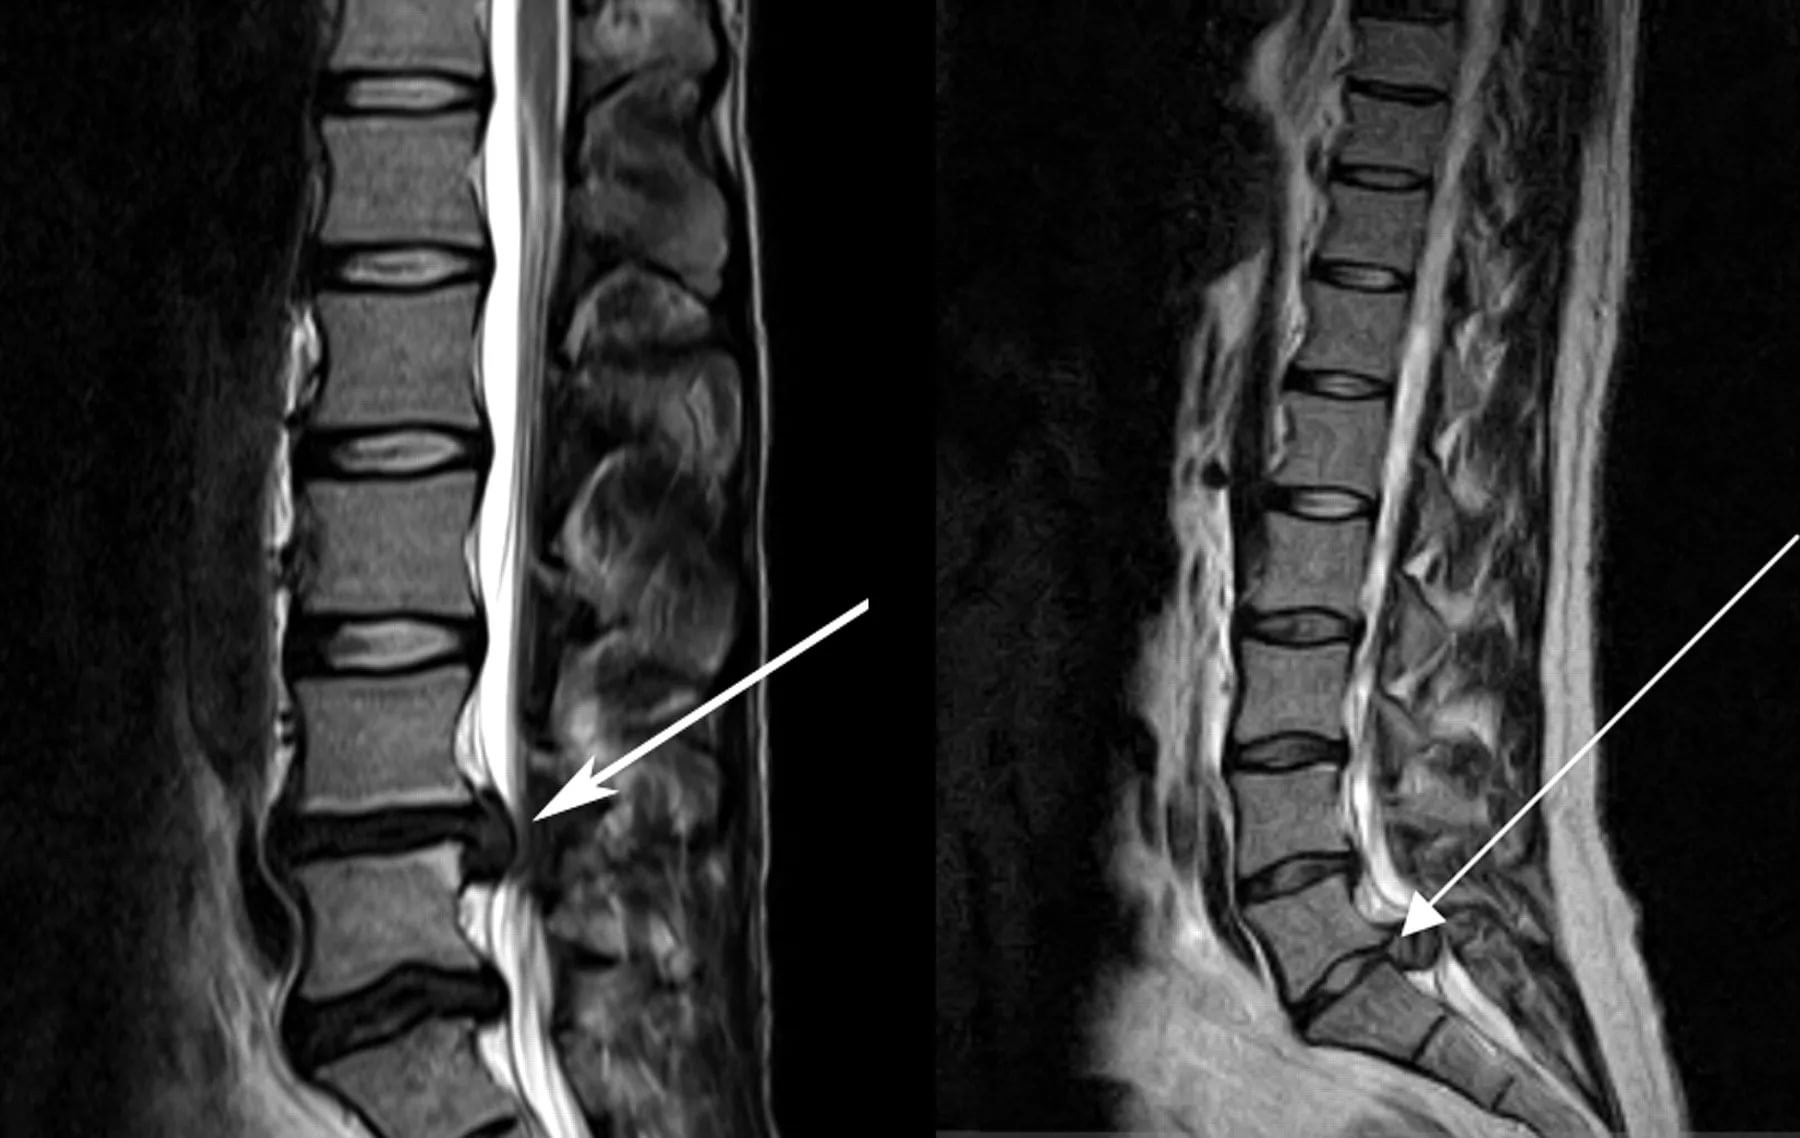

- Рентгенограмма позволяет визуализировать косвенные признаки остеохондроза – сближение позвонков. Но состояние ткани межпозвоночного диска не отражает – для этого дополнительно назначаются КТ, МРТ. Этими же методами удается диагностировать радикулит;

- Защемление нерва определяется по результатам электронейрограммы, МРТ, КТ. Мануальный осмотр также бывает достаточно информативен, ведь компрессия способна вести к снижению рефлексов, чувствительности;

Для выявления различной этиологии новообразований в спинном мозге, позвоночнике, мягких тканях проводят магнитно-резонансную и компьютерную томографию.

КТ – компьютерная томография. Это обследование проводится посредством рентгеновских лучей, что в итоге дает трехмерное изображение необходимых участков тела. Принцип работы происходит посредством серии снимков с разных точек, углов и последующего моделирования.

МРТ – магнитно-резонансная томография, которая работает по тому же принципу, что и КТ. Однако тип волн при МРТ отличается, потому как используются электромагнитные, что позволяет получать «ответ» от тканей, на которые идет воздействие.